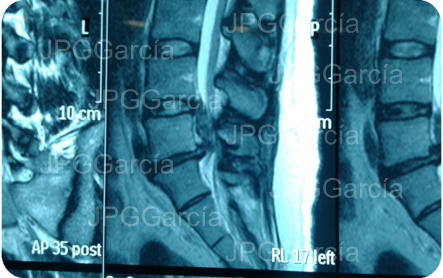

Hernia de disco lumbar extrusa L5 S1 (cortes

sagital y coronal en resonancia magnética)

Hernia de disco lumbar extrusa L5 S1 (cortes sagital y coronal en resonancia magnética)